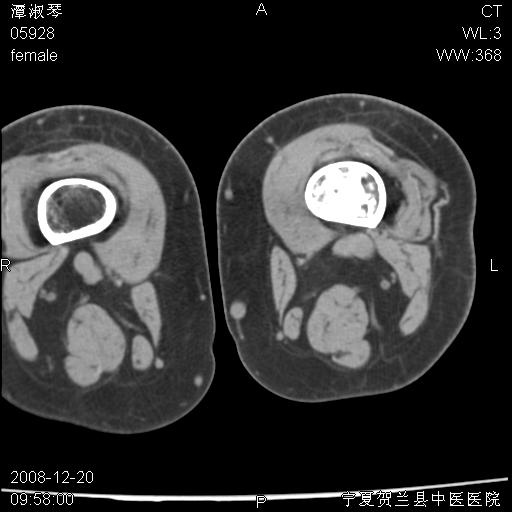

标题: CT17526:请各位看看是啥?

内生软骨瘤?骨梗死?

考虑内生软骨瘤可能性大

考虑-----骨梗死+退变

支持骨梗死,退行性骨关节病,膝关节积液.

考虑骨梗死可能性大

支持骨纤或内生软骨瘤或骨梗死,退行性骨关节病,膝关节积液.

骨梗死可能性大

左股骨下段骨梗死。双膝退变。

支持:内生软骨瘤或骨梗死!另:退行性骨关节病,膝关节积液。

左胫骨下端松质骨及髓腔内可见点片状高密度灶,骨皮质无明显膨胀及变薄。病变范围较长。支持骨梗死,退行性骨关节病,膝关节积液